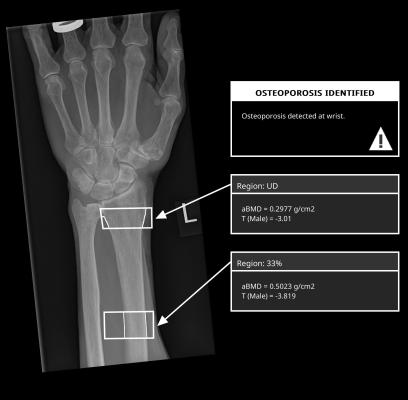

An X-ray image showing output from DensityScan, powered by IBEX BH. X-ray image taken from a published case study by the University of Exeter (Development of an opportunistic diagnostic prediction algorithm for osteoporosis and fragility fracture risk estimates from forearm radiographs (The OFFER1 Study)). https://ore.exeter.ac.uk/repository/handle/10871/134475

By harnessing the capabilities of IBEX BH, DensityScan measures subregional areal bone mineral density (aBMD) and estimates the T-score from wrist X-ray images. This technology provides earlier identification of osteoporosis, with the result automatically available to clinicians in secondary captures archived by the MUSICA workstation. This provides a starting point for assessing fracture risk and initiating diagnosis or treatment.